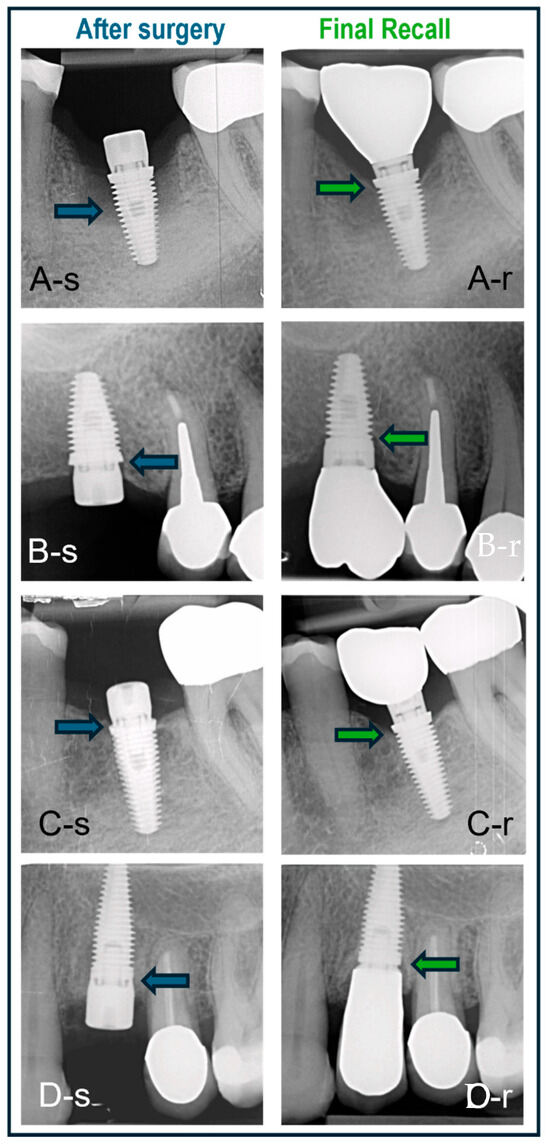

Survival and Bone Remodeling in Hybrid Surface Dental Implants Placed with 3 Surgical Protocols up to 5 Years: A Retrospective Practice-Based Cohort Study

Background: Single implants yield predictable survival and success using various treatment protocols. Innovations in design and surface texture improved survival and ensured crestal bone stability, crucial to avoiding biological complications. This study focuses on survival and peri-implant crestal bone remodeling during healing [...] Read more.

Background: Single implants yield predictable survival and success using various treatment protocols. Innovations in design and surface texture improved survival and ensured crestal bone stability, crucial to avoiding biological complications. This study focuses on survival and peri-implant crestal bone remodeling during healing and function of single hybrid-surface implants (Machine Surface Coronal, MSc, Southern Implants Pty Ltd., Irene, South Africa), featuring a minimally rough coronal region and moderately rough body. The specific aims were firstly to compare the clinical outcome between 3 surgical protocols and secondly to assess whether the outcome is affected by macroscopic implant design. Methods: Clinical records of 120 consecutively placed single MSc-implants in private practice were scrutinized after 12–62 months in function. Implants were placed using one of three surgical protocols as selected by the surgeon based on clinical judgment and treatment indication: flap-healed surgery with healing abutment (HA), flapless surgery with HA, or immediate implant placement (IIP) with HA. Six different implant types, albeit with the same MSc-surface feature, were utilized, based on individual clinical indications. Radiographical crestal bone level changes over time were analyzed and effect of implant design, gender, smoking status and surgical protocol was explored. Results: 101 implants was available for analysis. Six implants failed prior to loading (5%); 30% in smokers versus 3.3% in non-smokers. Initial bone remodeling, due to biologic width formation, was 0.762 mm (SD 0.940) at time of loading and 0.933 mm (SD 1.057) after 2 years (p = 0.07). Steady state bone levels at final recall (12–62 months; mean 24) were irrespective of implant type (p = 0.51), surgical protocol (p = 0.10), gender (p = 0.557) or smoking habit (p = 0.27). 54% of the implants showed bone gain between loading and final, whereas only 3% had bone loss above 3 mm. Conclusions: Under daily clinical conditions, MSc-hybrid implants yield predictable clinical outcomes in line with contemporary implant systems, irrespective of implant length and diameter. A 5.9% early failure rate was found irrespective of smoking status, with no late failures. Failure rate dropped to 3.3% when smokers were excluded. Crestal bone remodeling at the time of loading, mimicking biologic width formation, as well as bone level changes over time, is indicative of a healthy peri-implant steady state irrespective of the surgical protocol. Full article

Figure 1